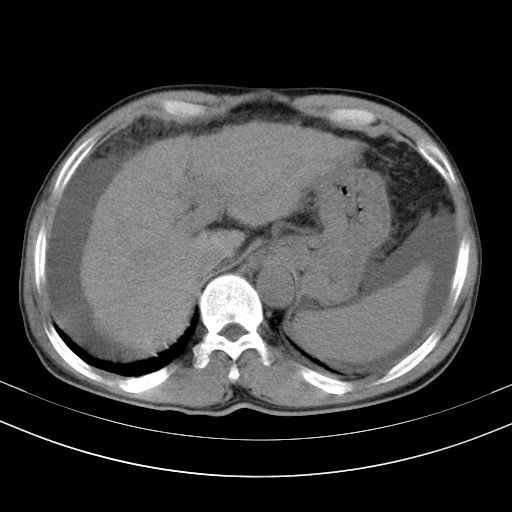

以下是引用随光逐影在2010-2-28 10:23:00的发言:[br]1)考虑肝癌;建议行ct增强扫描检查。2)肝硬化,脾大,腹水。3)慢性胆囊炎。